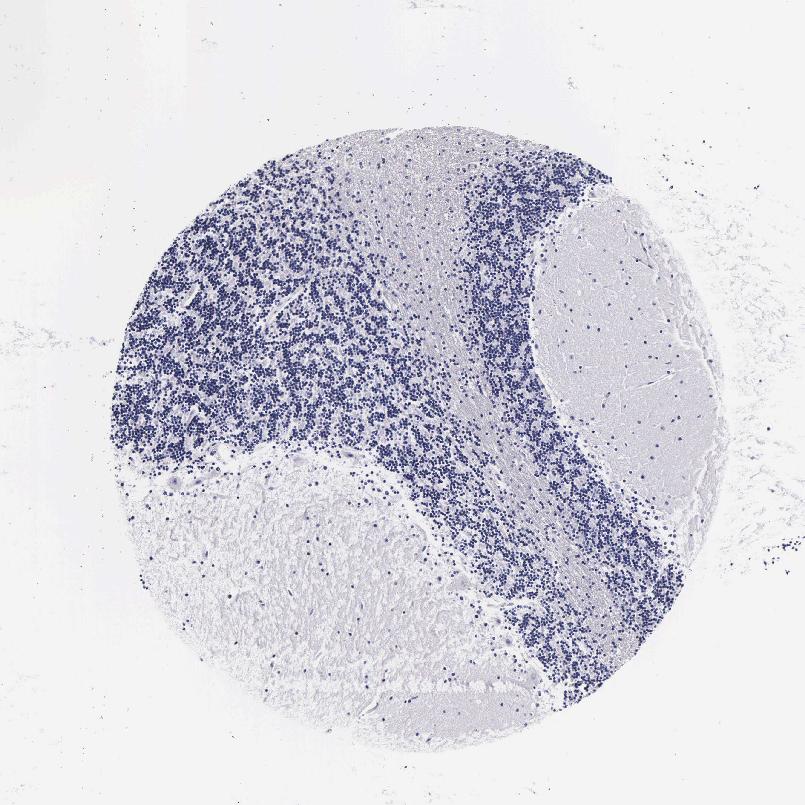

CEREBELLUM - Antibody stainingi

Antibody staining in the annotated cell types in the current human tissue is reported as not detected, low, medium, or high, based on conventional immunohistochemistry profiling in selected tissues. This score is based on the combination of the staining intensity and fraction of stained cells.

Each image is clickable and will lead to virtual microscopy that enables deeper exploration of all samples and also displays staining intensity scores, fraction scores and subcellular localization as well as patient and tissue information for each sample.

Antibody HPA000873

Purkinje cells Not detected

Cells in granular layer Not detected

Cells in molecular layer Not detected